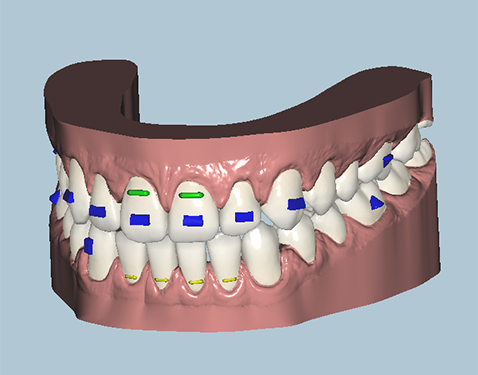

Orthodontist Proposal

After all materials are gathered, an orthodontist creates the movement proposal for the doctors approval. This is done through an on-line link that can be viewed in each stage of the process in 3D. Changes can be requested as needed or the proposal is approved for production.